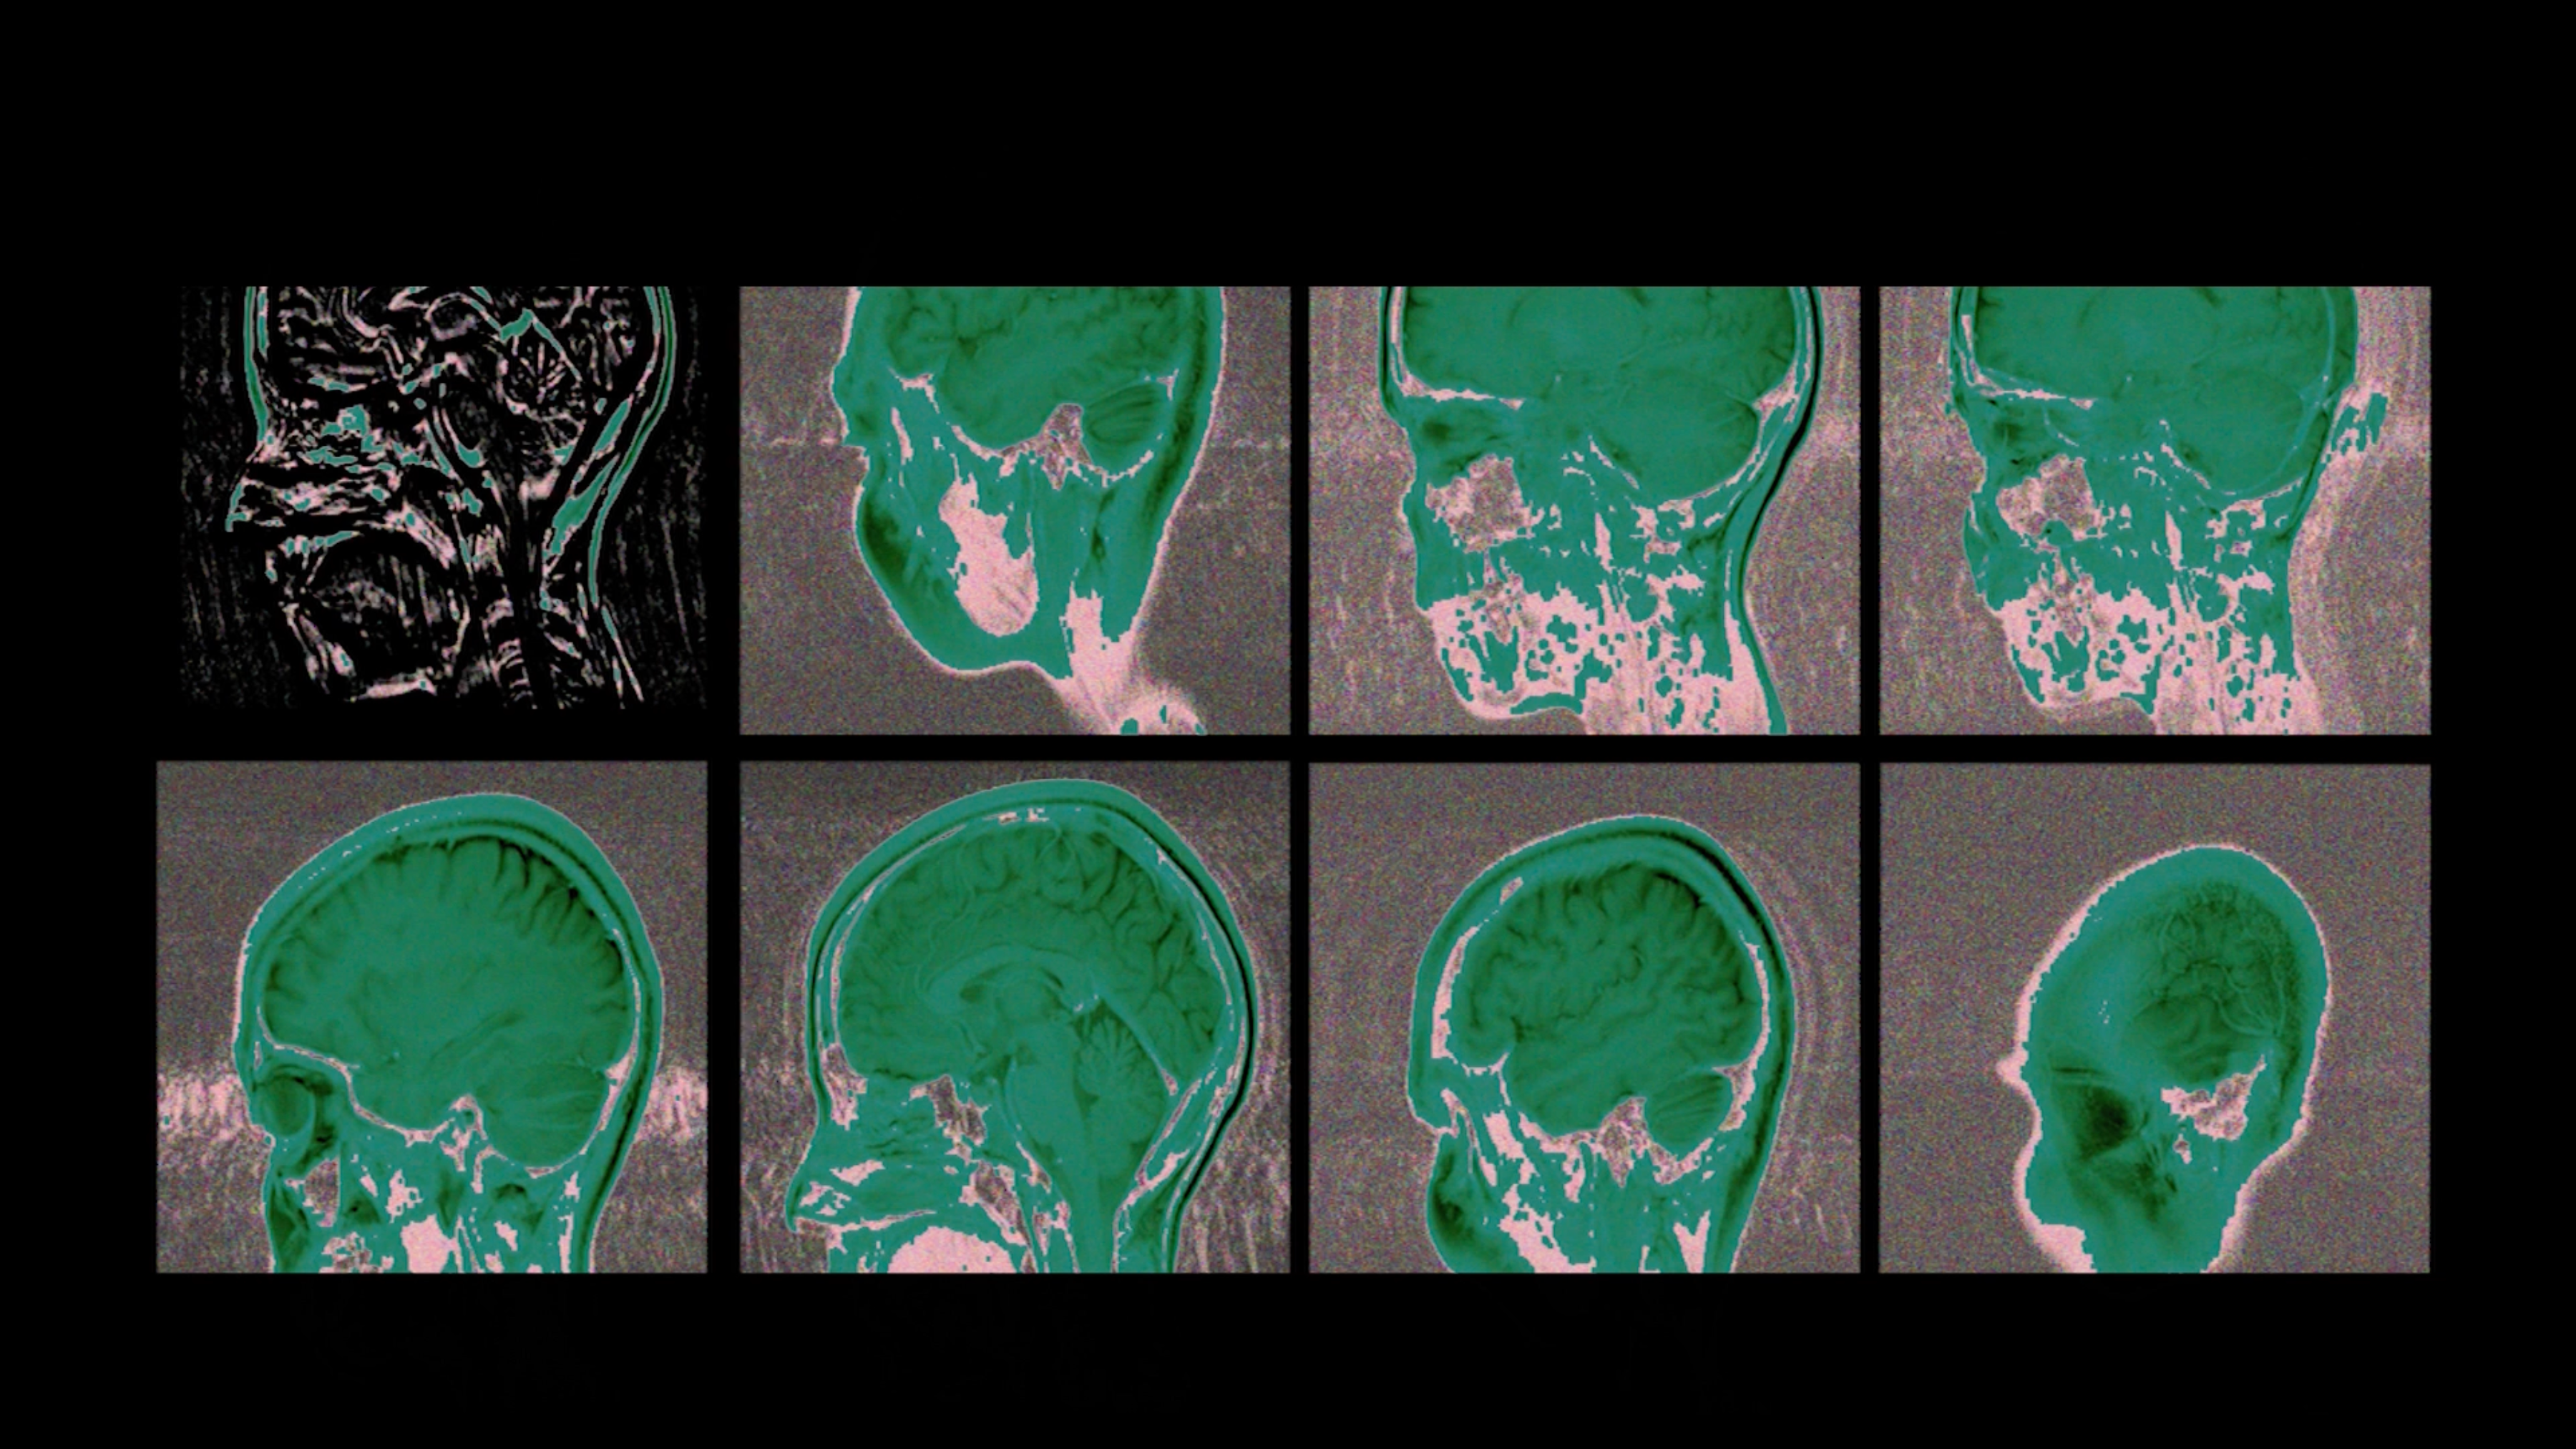

Active Brain in Non-Real Time

2021

video installation